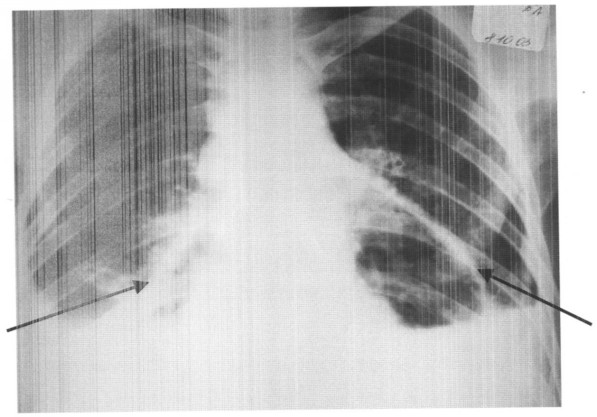

Способ осуществляют следующим образом. Больному с экссудативным сдавливающим перикардитом выполняют пункцию и дренирование полости перикарда. Затем по катетеру вводят воздух до 50% объема от количества удаленной из полости перикарда жидкости и создают пневмоперикардиум. Осуществляют рентгенологическую и эхокардиографическую оценку толщины перикарда, и при толщине перикарда менее 5-6 мм (см. чертеж) готовят больного к торакоскопической фенестрации перикарда.

Учитывая объем поражения сердца по данным МРТ, радикальное оперативное лечение – резекция опухоли больному не показана. При R-логическом и эхокардиографическом исследовании сердца, после пункции и дренировании полости перикарда, выявлено утолщение перикарда до 3-4 мм (см. чертеж). Операция – торакоскопическая фенестрация перикарда из левостороннего доступа.